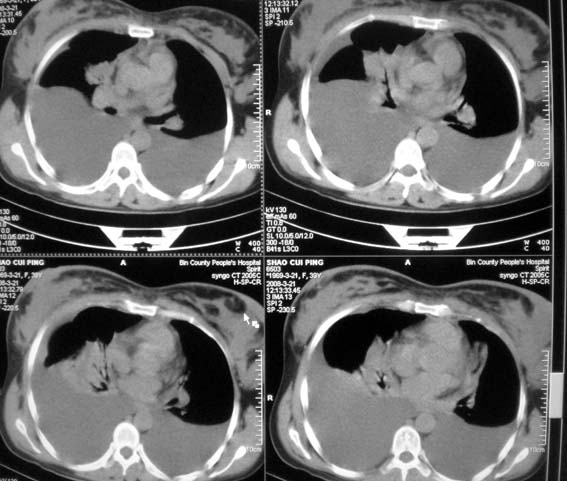

以下是引用zsl6918在2008-3-21 21:41:00的发言:[br]胸腔积液,心包积液,明确性质有难度。常规思路考虑结核性,建议抽液化验明确。

以下是引用随光逐影在2008-3-21 23:13:00的发言:[br]1)右肺中叶及左肺上叶舌段感染性病变。2)右肺中叶周围型肺癌待排。3)双侧胸腔积液并双下肺部分肺组织膨胀不全。4)心包积液。

以下是引用拾荒者在2008-3-22 21:21:00的发言:[br]胸腔积液、心包积液,双下肺膨胀不全,建议穿刺细胞学检查或抽液后进一步ct检查。